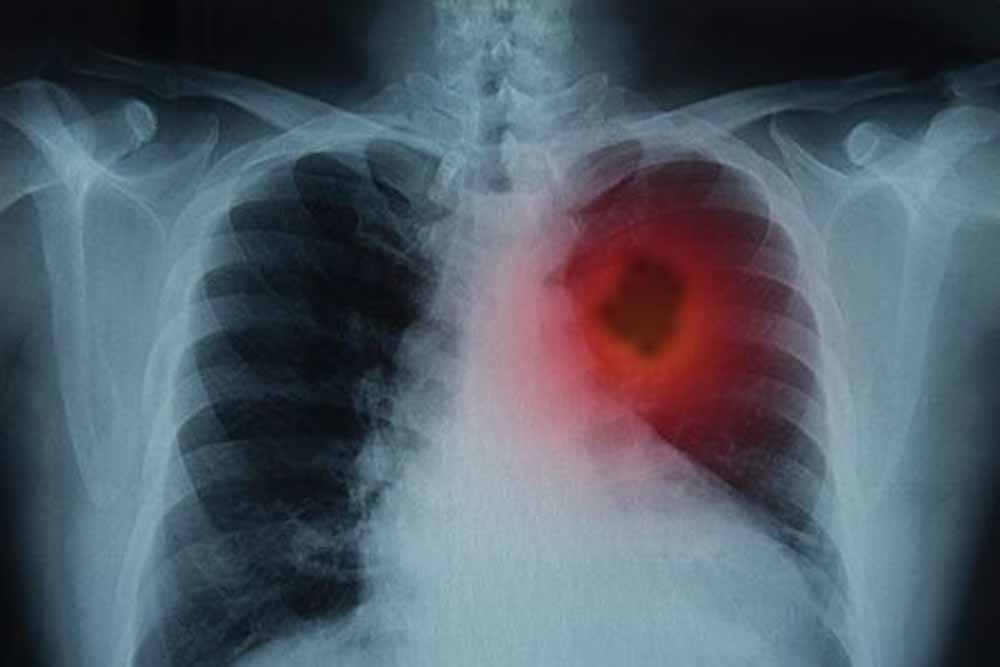

फेफड़ों के कैंसर से जूझ रहे लाखों लोगों के लिए विज्ञान की दुनिया से एक बहुत बड़ी और राहत भरी खबर आई है। दरअसल, वैज्ञानिकों ने एक ऐसा तरीका खोजा है जिससे फेफड़ों के ट्यूमर को उसकी सबसे बड़ी कमजोरी पर वार करके खत्म किया जा सकता है। जी हां, इस शोध के दौरान, उन्होंने एक बेहद जरूरी प्रोटीन की पहचान की। बता दें, यह प्रोटीन कैंसर कोशिकाओं को 'मरने' से बचाता है। ऐसे में, शोधकर्ताओं का कहना है कि अगर इस खास प्रोटीन की गतिविधि को रोक दिया जाए, तो कैंसर कोशिकाएं खुद-ब-खुद नष्ट होने लगती हैं और ट्यूमर सिकुड़ जाता है।

हाल ही में शोधकर्ताओं ने फेफड़ों के कैंसर की एक महत्वपूर्ण कमजोरी का पता लगाया है- एक ऐसा प्रोटीन, जिसे रोक दिया जाए तो कैंसर कोशिकाएं खुद को ही नष्ट करने लगती हैं। यह खोज न सिर्फ इलाज के नए रास्ते खोलती है, बल्कि भविष्य में ऐसे कई मरीजों के लिए जीवनदायिनी साबित हो सकती है, जिन्हें अब तक सीमित विकल्प ही उपलब्ध थे।